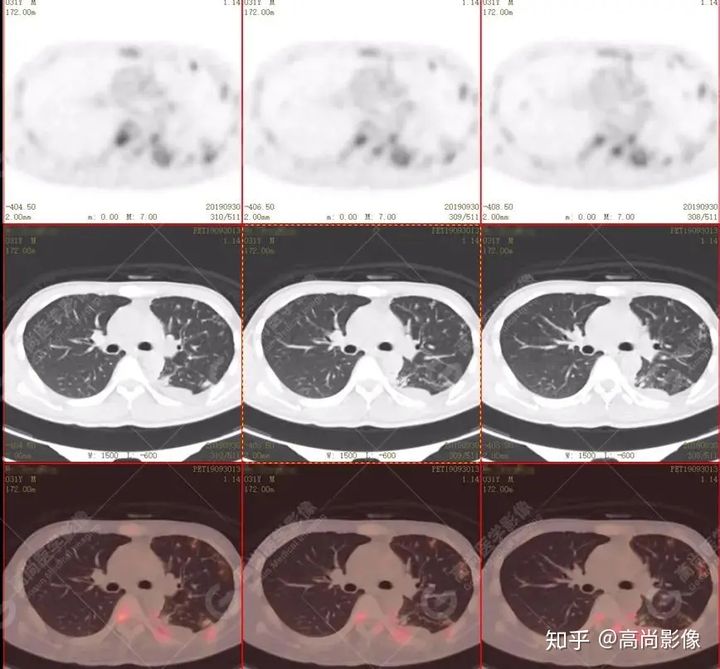

左肺上葉尖后段及下葉背段多發(fā)簇狀斑點(diǎn)狀高代謝灶